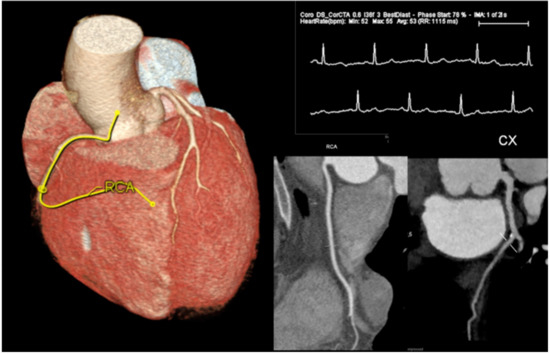

- Marano, R.; Rovere, G.; Savino, G.; Flammia, F.C.; Carafa, M.R.P.; Steri, L.; Merlino, B.; Natale, L. CCTA in the diagnosis of coronary artery disease. Radiol. Med. 2020, 125, 1102–1113. [Google Scholar] [CrossRef]

- Busse, A.; Cantré, D.; Beller, E.; Streckenbach, F.; Öner, A.; Ince, H.; Weber, M.A.; Meinel, F.G. Cardiac CT: Why, when, and how: Update 2019. Radiologe 2019, 59. [Google Scholar] [CrossRef]

- Rajiah, P.; Abbara, S. CT coronary imaging—A fast evolving world. QJM 2018, 111, 595–604. [Google Scholar] [CrossRef]

- Schicchi, N.; Mari, A.; Fogante, M.; Esposto Pirani, P.; Agliata, G.; Tosi, N.; Palumbo, P.; Cannizzaro, E.; Bruno, F.; Splendiani, A.; et al. In vivo radiation dosimetry and image quality of turbo-flash and retrospective dual-source CT coronary angiography. Radiol. Med. 2020, 125, 117–127. [Google Scholar] [CrossRef]

- Cury, R.C.; Abbara, S.; Achenbach, S.; Agatston, A.; Berman, D.S.; Budoff, M.J.; Dill, K.E.; Jacobs, J.E.; Maroules, C.D.; Rubin, G.D.; et al. CAD-RADSTM Coronary Artery Disease—Reporting and Data System: An Expert Consensus Document of the Society of Cardiovascular Computed Tomography (SCCT), the American College of Radiology (ACR) and the North American Society for Cardiovascular Imaging (NASCI). Endorsed by the American College of Cardiology. J. Cardiovasc. Comput. Tomogr. 2016, 10, 269–281. [Google Scholar] [CrossRef] [PubMed]